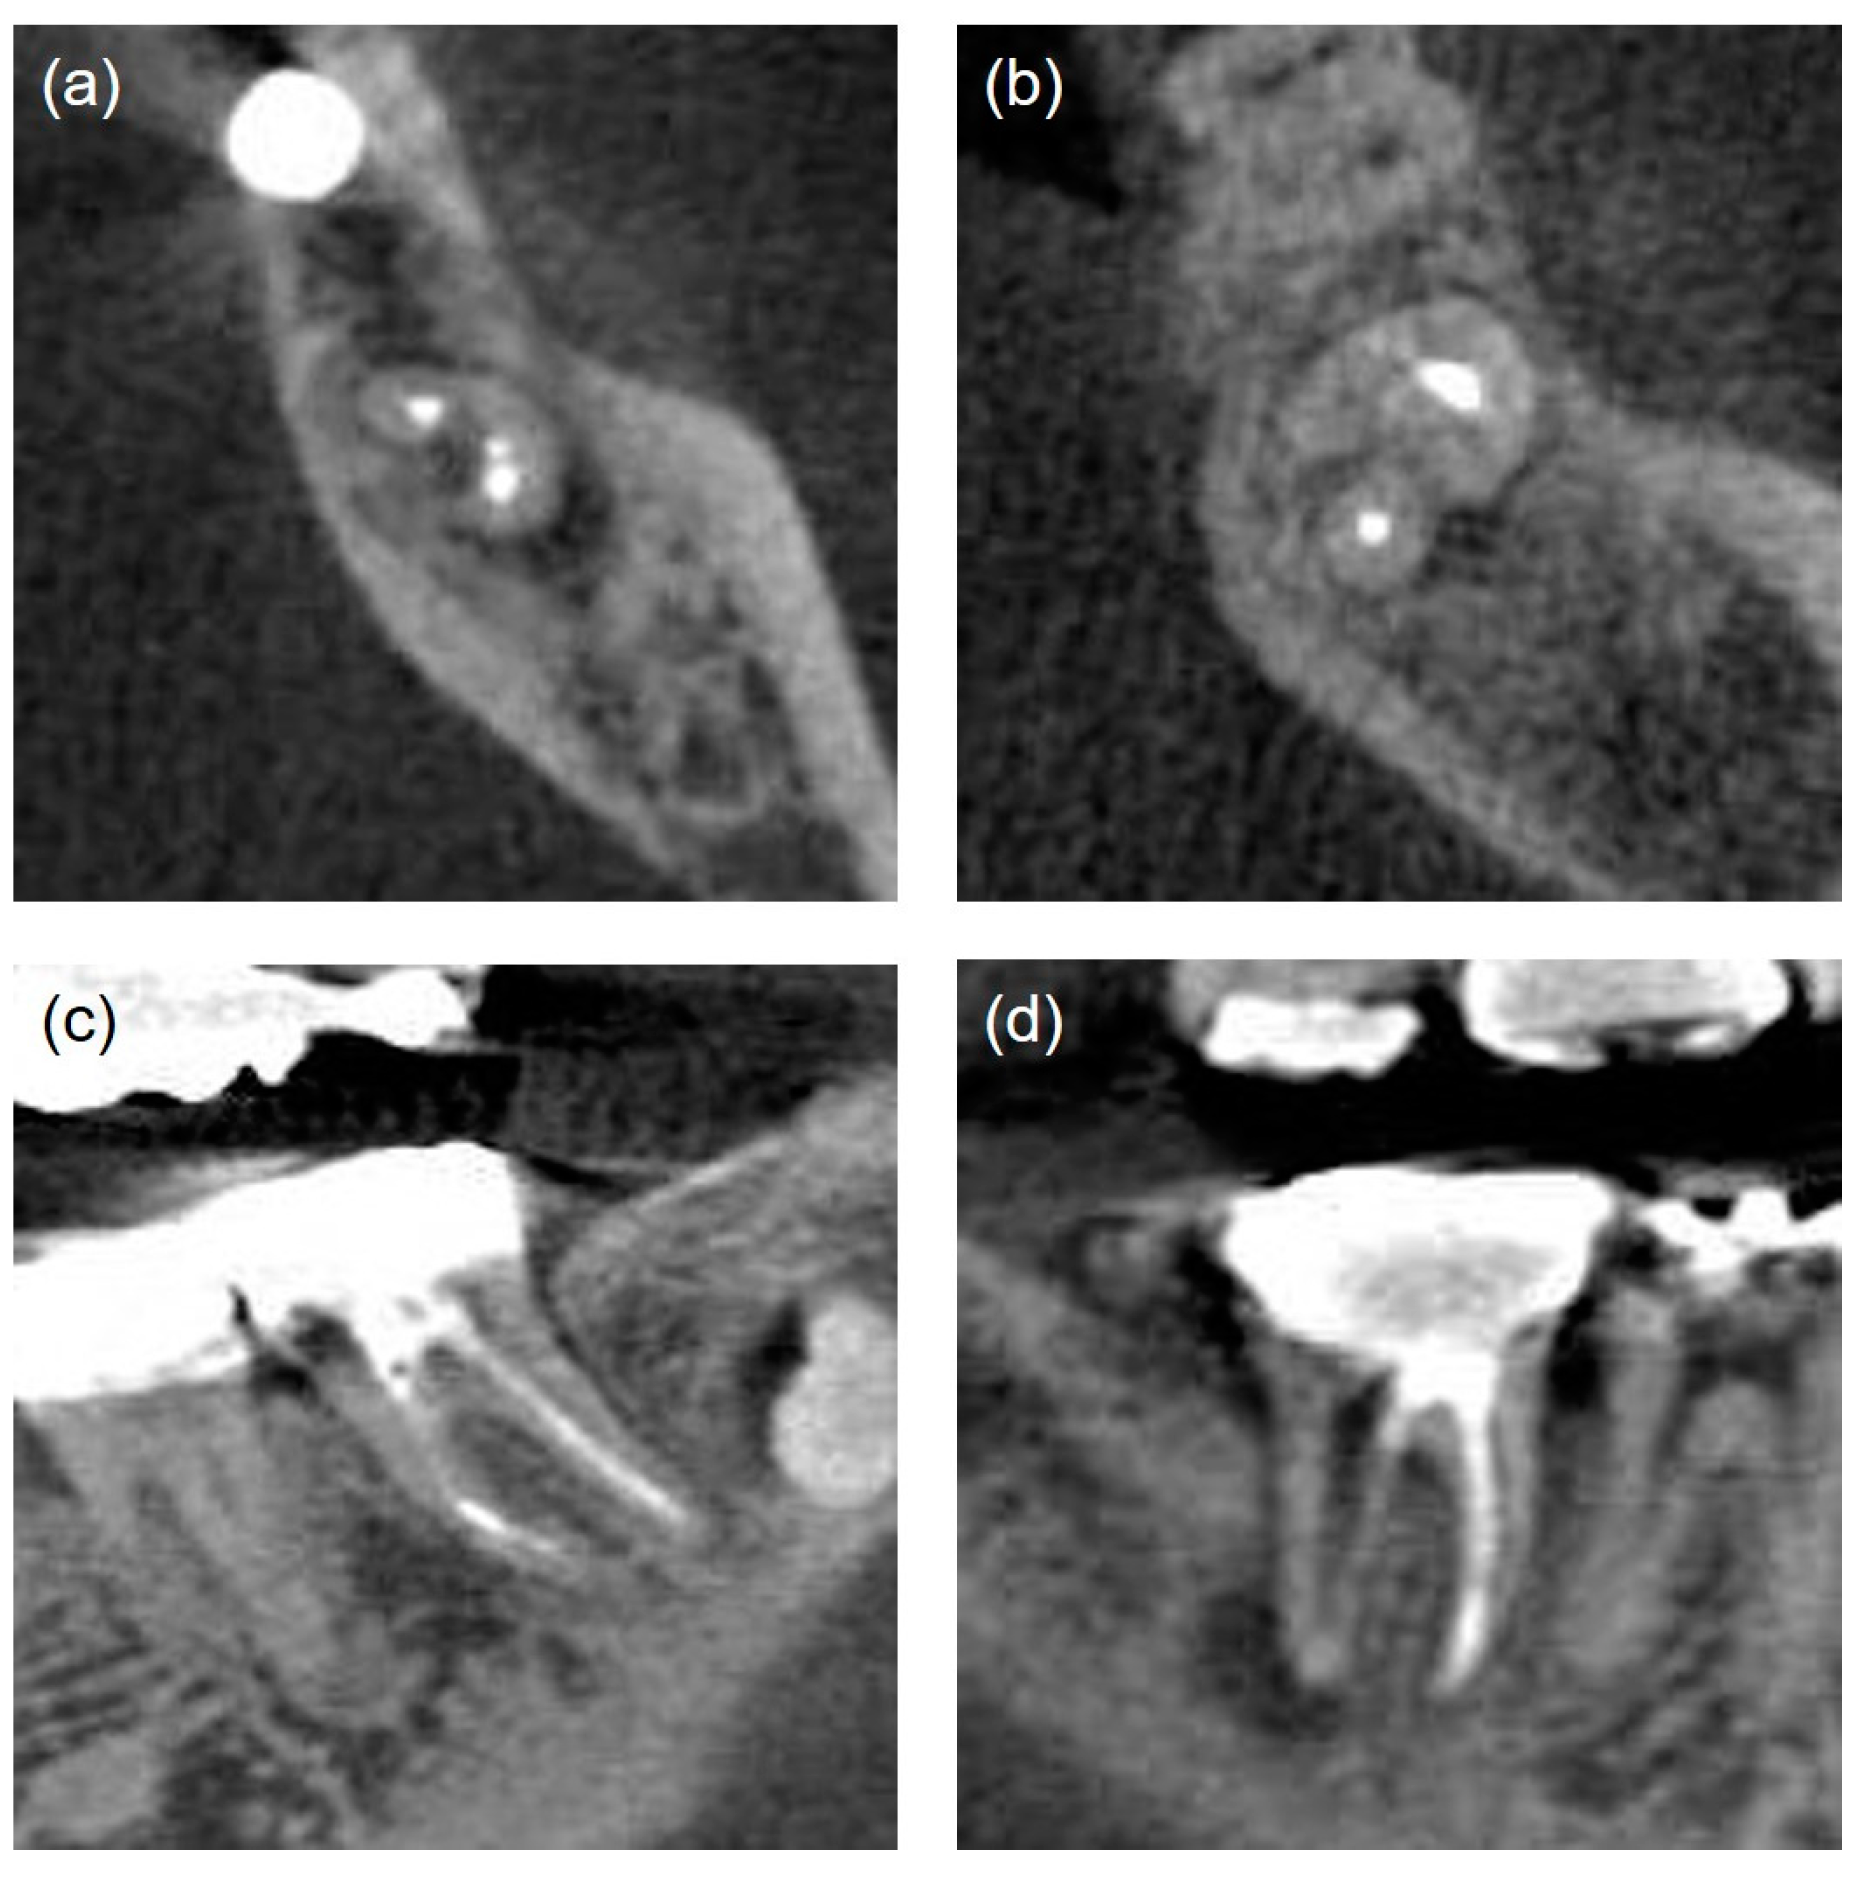

| Poor | Non-uniform radiodensity, with the canal space visible laterally and apically. Isthmus area that had not been treated (Figure 3a) | |

| Missed canals [18] | Unfilled canals appearing from cemento-enamel junction to apex including canals splitting from a main canal at coronal, mid, or apical third (Figure 3b) | |

| Iatrogenic problems | File separation. Perforation (present/absent) (Figure 3c,d) | |